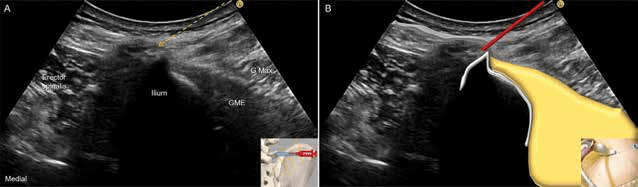

흉요근막 사이의 상둔신경을 목표로 하는 평면내 접근법으로 수압박리술을 시행했습니다. 수압박리술 - 그림 8. 흉요근막(thoracolumbar fascia) 사이의 상둔신경(단축 영상)을 Figure 8. 그림 8. 흉요근막(thoracolumbar fascia) 사이의 상둔신경(단축 영상)을 목표로 하는 평면내(lateral to medial) 접근법입니다.

흉요근막을 표적으로 하는 측면-내측 평면내 접근법을 통해 효과적인 수압박리술을 수행했습니다. 수압박리술 - 그림 10. 흉요근막을 목표로 하는 평면내(lateral to medial) 접근법(A)입 Figure 10. 그림 10. 흉요근막을 목표로 하는 평면내(lateral to medial) 접근법(A)입니다. 해당하는 개략도(B)입니다.

장골능 상연을 목표로 하는 평면내 접근법으로 수술 후 진통에 효과적인 수압박리술을 시행했습니다. 수압박리술 - 그림 11. 장골능(iliac crest) 상연을 목표로 하는 평면내(lateral to Figure 11. 그림 11. 장골능(iliac crest) 상연을 목표로 하는 평면내(lateral to medial) 접근법(A)입니다. 해당하는 개략도입니다.